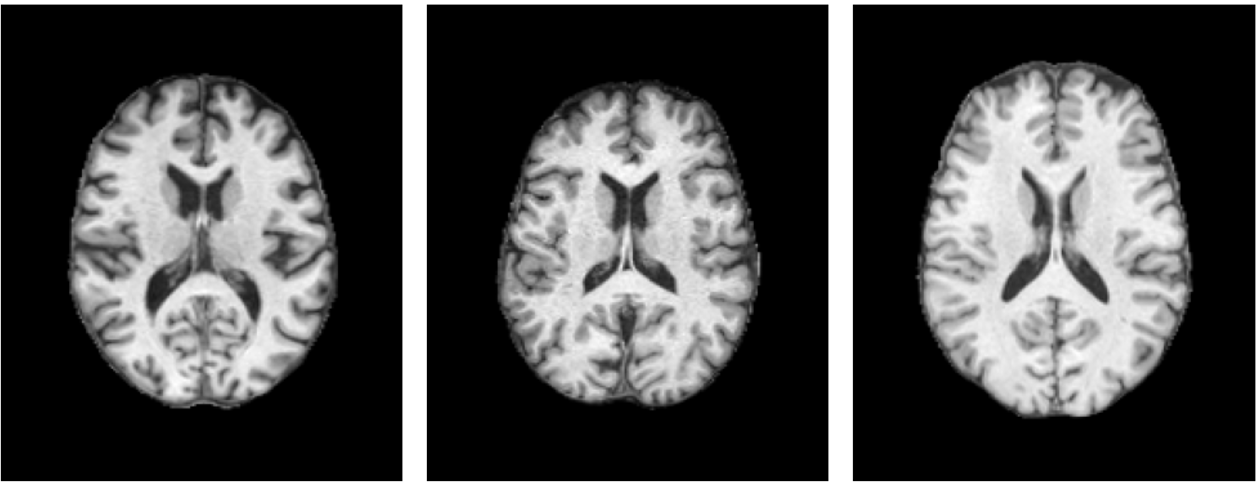

In brain imaging, 3D structural MRI scans from different populations share a high degree of visual and anatomical similarity. For example, Figure 1 shows brain images of patients diagnosed with Alzheimer’s disease, Parkinson’s disease, and a healthy control. Rather than being constrained by the limited availability of labeled samples, there exists an unmet opportunity to aggregate diverse datasets spanning both healthy and diseased populations to train large-scale models that learn general representations. Such a model would have a deep understanding of the 3D brain and its components, accounting for wide variability across the population and generalizing well across datasets, disorders, and diagnostic tasks, particularly in situations with limited labeled data available.

Figure 1: Brain MRI slices of patients with Alzheimer’s disease [30] (left), Parkinson’s disease [26] (centre) and a healthy control [22] (right), showing the similarity of brain images despite different diagnoses.